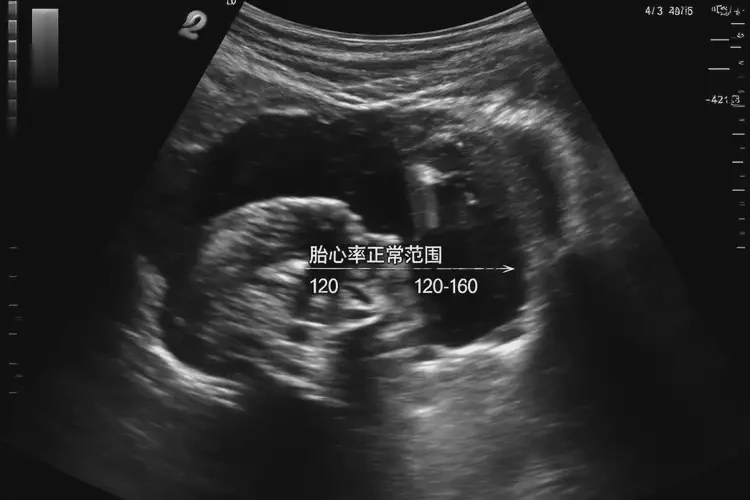

在孕早期,胎心率可能會(huì)有較大的波動(dòng),通常在120-180次/分鐘之間都被認(rèn)為是正常的。雖然181次/分鐘略高于正常范圍的上限,但并不意味著胎兒一定有問題。以下幾點(diǎn)可以幫助我們更全面地理解這一情況:

1. 正常范圍:胎心率的正常范圍是120-180次/分鐘。在孕早期,由于胎兒心臟發(fā)育尚未完全成熟,胎心率可能會(huì)有較大的波動(dòng)。

孕周胎心率正常范圍(次/分鐘)

5周120-180

6周120-160

7周120-160

8周120-160

孕5周1天胎心率181還能保住嗎(圖1)